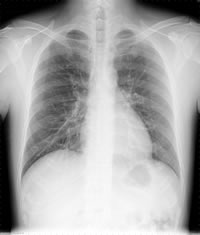

ひとつは胸部レントゲンです。肺に異常がないかどうか、かなりのことがわかります。レントゲンでは、普通の肺は心臓を間に挟んで黒く写り、中を走っている血管が白く写ります。

COPDはある程度進行すると、胸部レントゲンでも診断できます。肺胞が破れて拡張するので正常な肺(写 真(1))に比べて肺全体が大きくなり、肺とおなかの臓器を区切っている横隔膜の位置が下へ下がります。また心臓は膨らんだ肺に押されて長細くなります (写真(2))。

さらにその肺をCTで見ると、正常の肺構造では一つひとつの肺胞は小さくて見えないため、全体に均一な灰 色に写ります(写真(3))が、肺胞が破れた肺は空気の部分が黒く写ります(写真(4))。黒く写った部分はまったく酸素の取り込みができないため、いく ら呼吸をしても酸素が血液の中に入ってこない状態となり、「息苦しさ」を感じるのです。

| (1)正常な肺のレントゲン | (2)COPDの肺のレントゲン |

| (3)正常な肺のCT | (4)COPDの肺のCT |

| 【COPD】レントゲンでは、正常の人に比べて肺が膨張し、横隔膜をおし下げ、心臓も圧迫しているのがわかる。CTでは、正常の肺は均一な灰色で血管の白い点がみられるが、COPDでは肺が破壊され黒っぽくなり、血管が少なくなっている。 | |